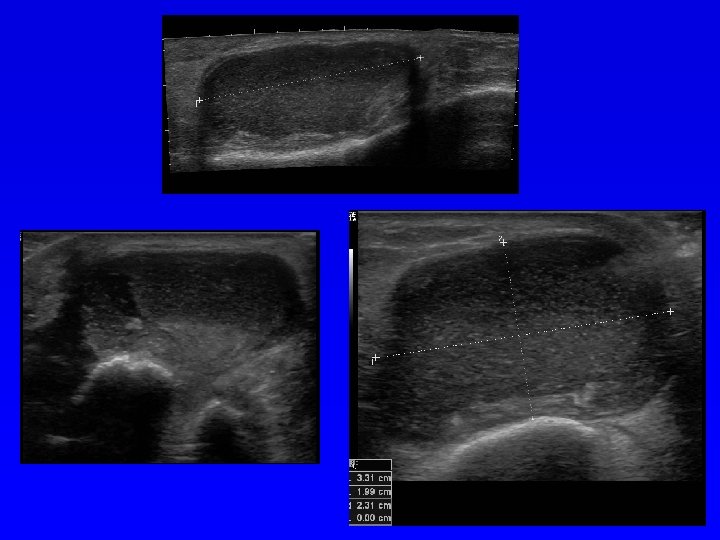

Ultrasonografie Podle echogenity (odrazivosti) lze uspořádat tkáně: Kost (výrazně echogenní), vazivo, sval, tuk, chrupavka, tekutina (minimální echogenita). Anechogenní struktura- černá Hypoechogenní struktura- šedá Hyperechogenní - bílá Diagnostika měkkých tkání Diagnostika nádorů Diagnostika VDK Zjištění výpotku v kloubu Další využití